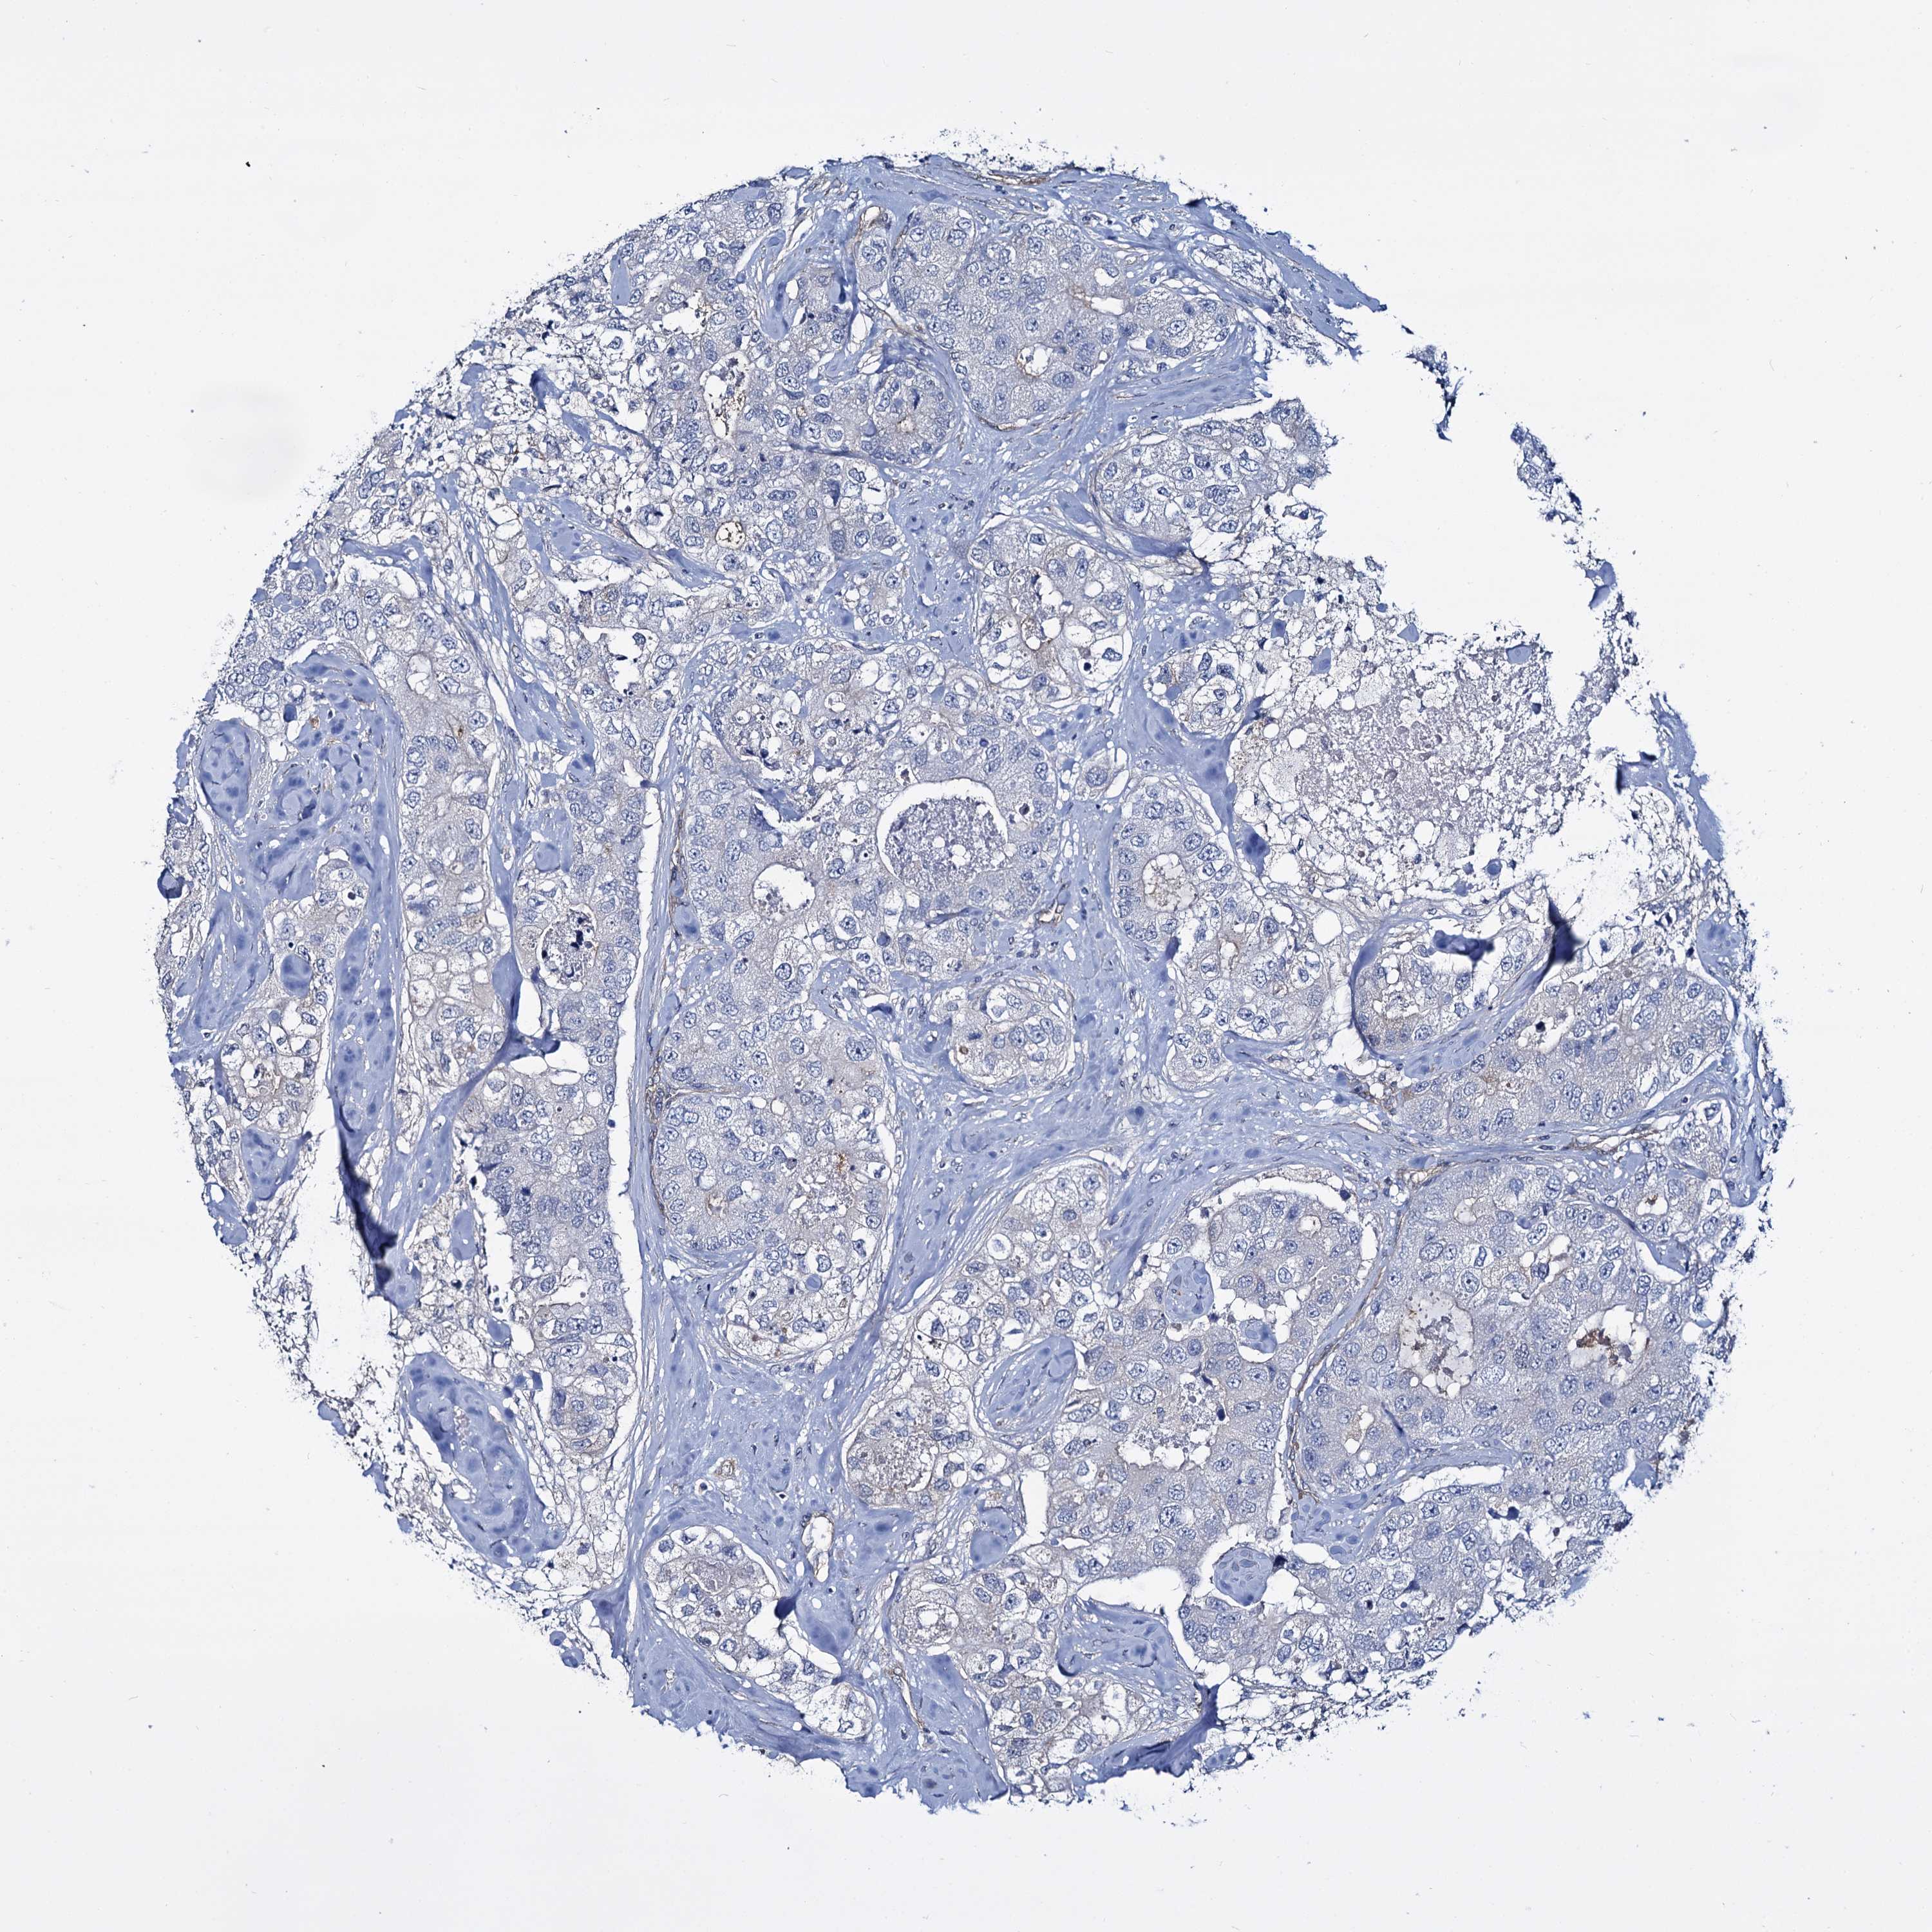

CANCER BREAST CANCER Show tissue menu

BRCA TCGA BRCA VALIDATION PROTEIN EXPRESSION